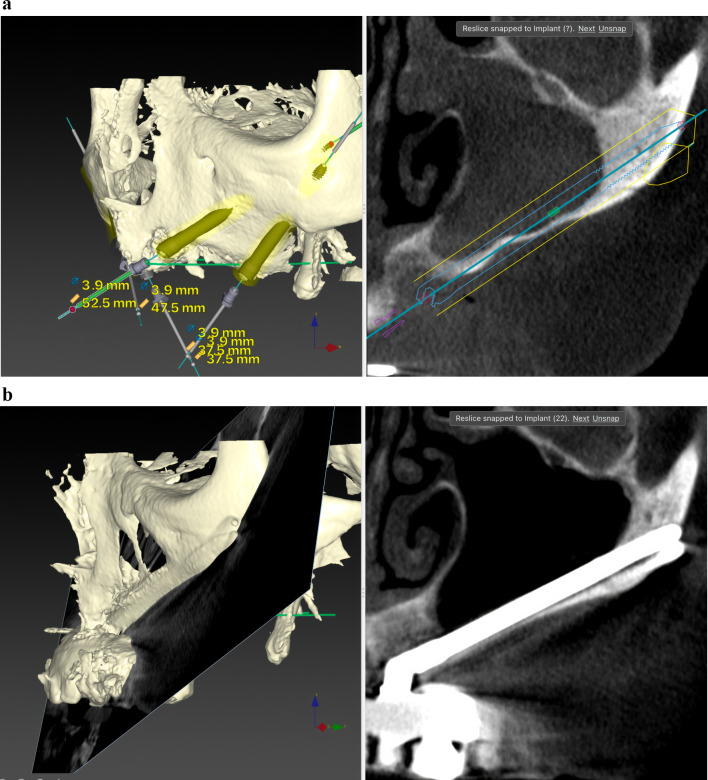

Results: Twenty patients were treated. Ten patients received two ZIs and regular implants; one received three ZIs plus regular implants, and nine received four ZIs. Fifty-nine ZIs were placed: thirty-six (61%) Straumann ZAGA-Flat implants and twenty-three (39%) Straumann ZAGA-Round implants. Four patients (20%) presented earlier sinus floor discontinuities. Fifteen patients (75%) had prior sinus opacities. Nineteen patients were followed for between 38 and 53 months (mean 46.5 months). One patient dropped out after 20 months. When comparing pre-surgical CBCT with post-surgical CBCT, 84.7% of the sites presented identical or less sinus opacity; nine locations (15%) showed decreased, and another nine increased (15%) post-surgical sinus opacity. Fifty-three ZIs (89.8%) maintained stable soft tissue. Six ZIs had recessions with no signs of infection. ZIs and prosthesis survival rate was 100%.